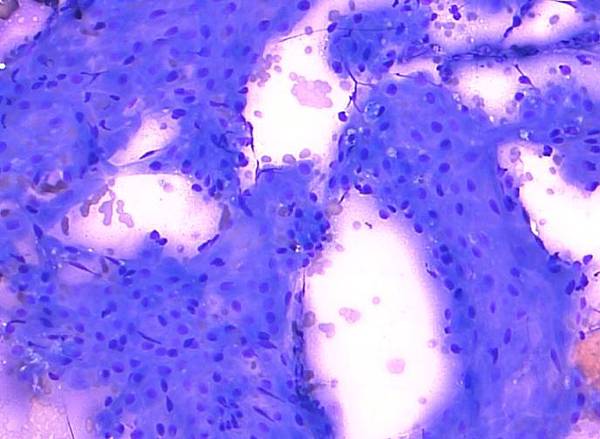

• 犬高惡性度肥大細胞瘤(high-grade MCT)

所謂高惡性度(high-grade)與低惡性度(low-grade)是一種肥大細胞瘤的病理分級方式,病理獸醫師會依據腫瘤細胞的有絲分裂指數、多核細胞數量、異型性細胞核及細胞核大小不一等特徵進行腫瘤分級。近年來也發展出利用細胞學檢查來評估高惡性度或低惡性度,在臨床上是一個快速簡單的方法。